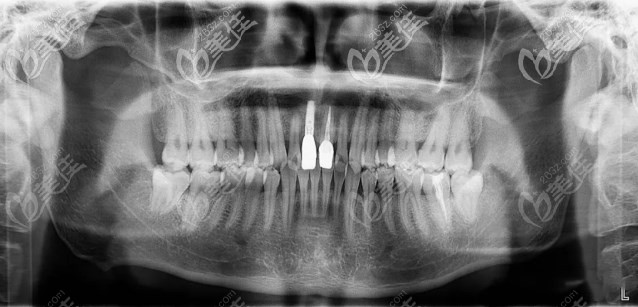

經(jīng)口腔數(shù)據(jù)分析,間隙充足,鄰牙健康,適合種植。

CT:顯示大門牙牙位牙槽骨唇腭向距離月7.78mm,牙槽嵴頂?shù)奖堑准s28mm,適合種植牙。